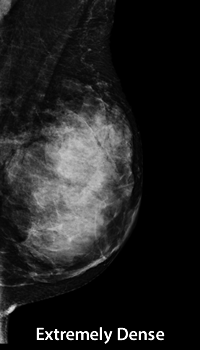

A mammogram is used to identify breast density. The radiologist reading your mammogram will determine your density based on a four-level scale (A, B, C, D) approved by the American College of Radiology. The Breast Density Notification and Awareness Bill, approved by North Carolina legislation, requires all mammography providers to inform women of their breast density level as interpreted on their mammogram. This information will be included in the mammography report sent to you and your physician. Breast density is assessed each year and may vary based on radiologist interpretation, as well as naturally occurring changes in breast tissue.

A 4-level scale is used to categorize breast density:

Screening for women with dense breast tissue - Heterogeneously Dense (C) or Extremely Dense (D)

These breast tissue types are associate with increased risk for breast cancer because cancers can remain hidden. Women with dense breast tissue should continue having annual mammograms. Mammograms are the only medical imaging exam proven to reduce breast cancer deaths. Women with dense breasts should discuss with their physician whether supplemental imaging should be considered.